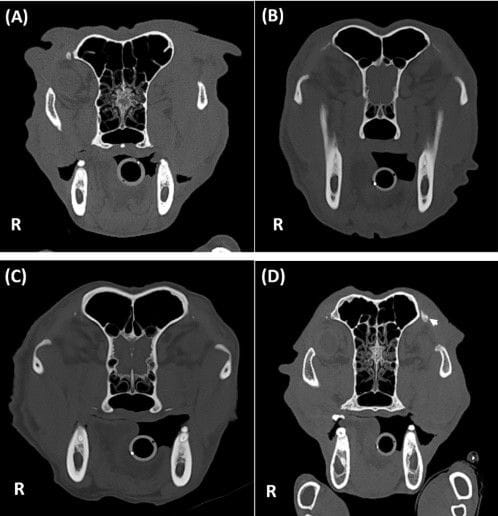

This retrospective descriptive study reviewed 402 canine head CT examinations performed at a single private referral hospital between January and December 2024. CT scans were evaluated for the presence of OL mineralization and characterized by laterality, symmetry, location within the ligament, size, attenuation, morphology, texture, margins, and number of lesions. Signalment (age, breed, sex, neuter status, weight), skull conformation, medical history, biochemical data (including calcium levels), CT indication, and concurrent mineralization at other sites were recorded. Statistical analyses included Chi-square or Fisher’s exact tests for categorical variables and Student’s t-test or Mann–Whitney U test for continuous variables, with Bonferroni correction applied.

Orbital ligament mineralization was identified in 157 of 402 dogs (39.1%). Lesions were consistently dorsally located (100%) and most commonly bilateral (86.6%) and symmetrical. Morphologically, mineralization was most frequently triangular, well-defined, heterogeneous, and focal. Median lesion size was 2.48 mm and median attenuation was 793 HU. OL mineralization was significantly associated with increasing age and body weight, non-brachycephalic skull conformation, normal (non-atrophied) frontal sinuses, and concurrent mineralization at other sites, particularly in the lungs and ears. Dogs with OL mineralization were significantly older and heavier than unaffected dogs. No significant associations were found with serum calcium levels, endocrine disorders, prior corticosteroid use, chronic kidney disease, facial trauma, orbital disease, or other pathological conditions.

Orbital ligament mineralization is a common finding in canine head CT studies, with a prevalence of 39.1% in this cohort. It is consistently dorsally located and typically bilateral and symmetrical. Its significant association with age, body weight, and other mineralization sites—without correlation to pathological conditions—supports its interpretation as a benign, incidental, age-related change without clinical significance.